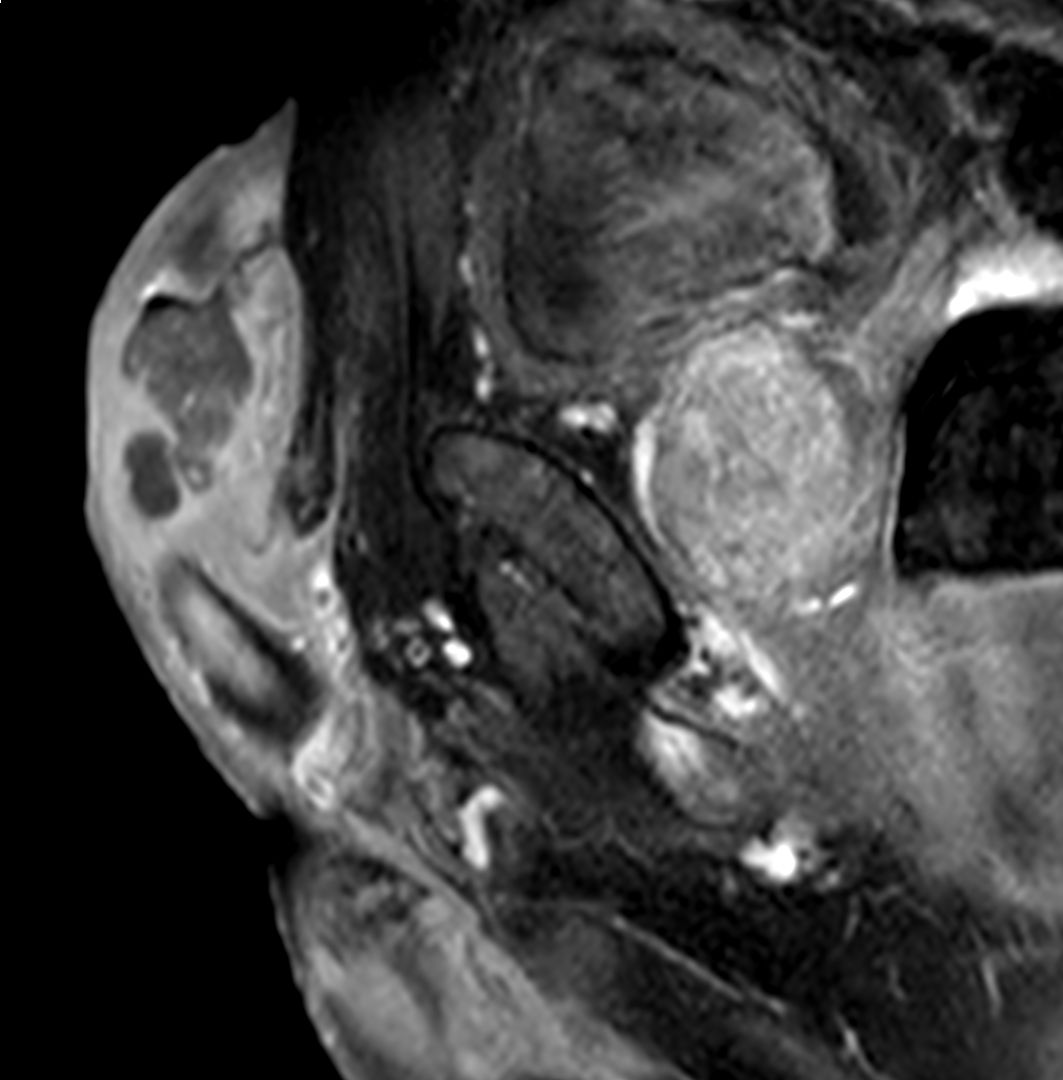

Patient with a penile carcinoma. ExamCard includes Compressed SENSE to shorten exam time, diffusion to achieve high contrast between background and lesions, and MultiVane XD for motion-free imaging in short scan time.

T2w TSE Compressed SENSE